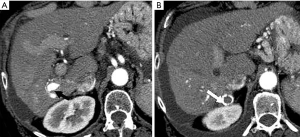

Because HCC remains amongst the most significant long-term sequelae of the cirrhotic liver, small HAPS when observed must carefully be distinguished from de novo HCC. The differentiation between HCC and HAPS is a critical clinical issue requiring a vigilant approach.

The major differentiating imaging features between HAPS and HCC are as follows: (I) a HAPS usually exhibits a peripheral location with a wedge-shaped appearance, straight margin, and cone-shape on three-dimensional reconstructed images. Normal vessels can be seen coursing through the area. (II) “Washout” is regarded as diagnostic for the differentiation of hypervascular HCC from non-tumorous HAPS. The equilibrium phase is also extremely useful in this differentiation as HCC usually arise as an area of heterogeneous low attenuation (or intensity), while the signal attenuation of a HAPS not arising with an HCC will not decrease below parenchymal background (Figure 16). (III) Repeat follow-up imaging procedures usually demonstrate the resolution or stability of a HAPS, as opposed to growth of an HCC.